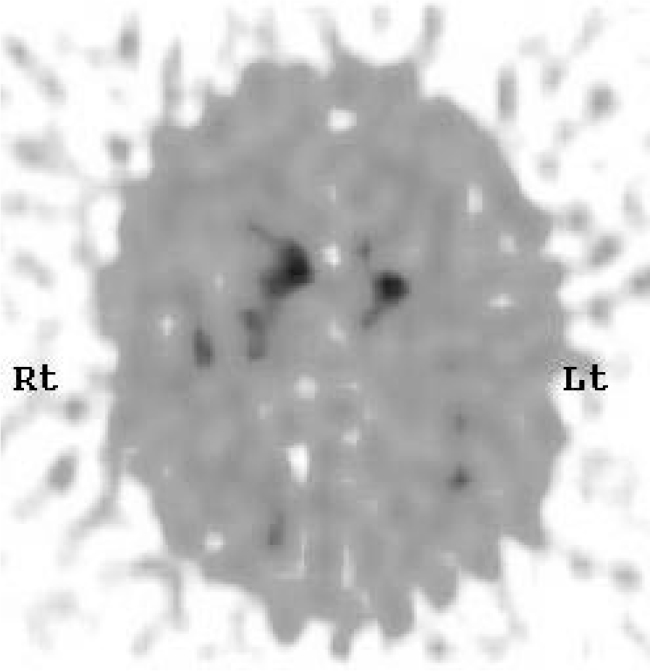

Single-photon emission computed tomography has been considered to be the gold standard scan in the diagnosis of dementia with Lewy bodies, showing reduced dopamine transporter activity in the basal ganglia. [123]I-FP-CIT SPECT (DaTSCAN; Fig. 3) uses a ligand that binds to the dopamine transporter molecule; this can highlight areas of nigrostriatal degeneration that lead to dementia with Lewy bodies. Studies assessing this show specificity of up to 90% and sensitivity of 75% (Reference Walker and WalkerWalker 2009), suggesting that DaTSCAN is more accurate than clinical diagnosis alone.

FIG 3 DaTSCAN for a patient with suspected dementia with Lewy bodies. The scan shows reduced tracer uptake in both putamina, with relatively normal uptake in the heads of caudate nuclei bilaterally. These findings are in keeping with dementia with Lewy bodies.